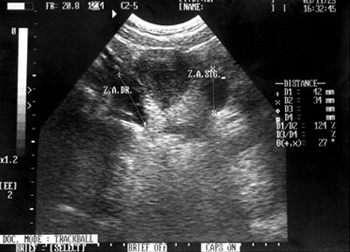

초음파(Ultrasonography)검사

신체에 무해한 초음파를 몸에 투사하여 간, 담낭, 비장, 췌장, 혈관계, 비뇨생식기계, 위장관을 포함한 질병의 유무, 병소의 크기와 양상을 진단하는데 필수적인 검사방법입니다. 일반적인 복강 내 장기 외에도 초음파를 통해 뇌실, 안구, 근골격계 및 관절 인대에 대한 평가를 시행하고 있습니다.